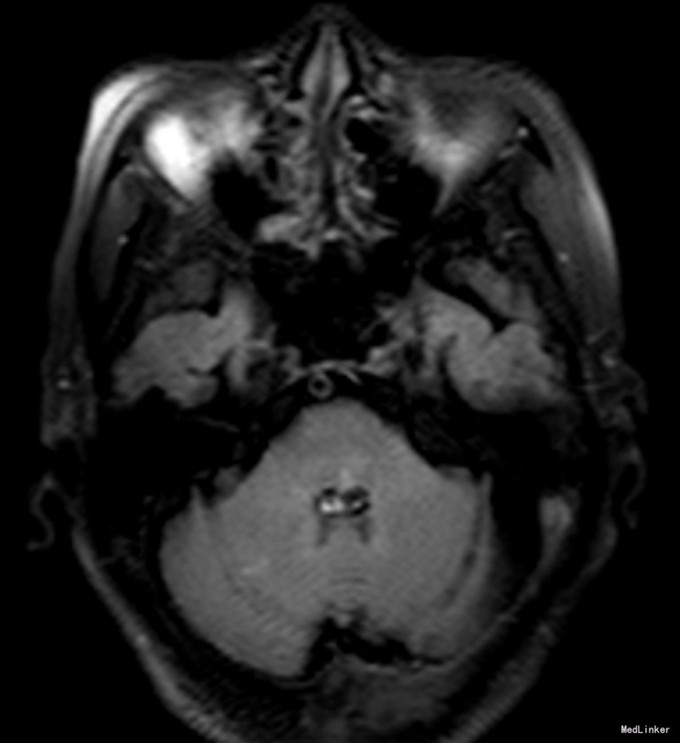

老年女性,急性起病。查体可见左眼内收受限,双眼右视时有水平眼震。影像学提示左侧桥脑背侧梗塞。与临床相符。考虑前核间性眼肌麻痹。 附上另一例前核间性眼肌麻痹头MRI,如图: